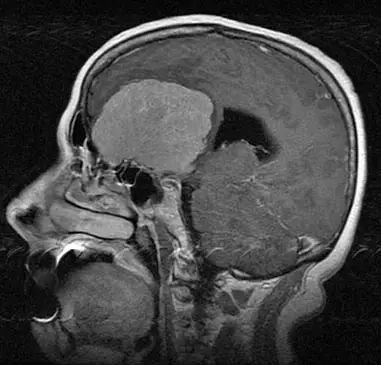

发生在颅颈交界部的脑膜瘤(MRI扫描,矢状位[左]和轴位[右])称为枕骨大孔脑膜瘤。枕骨大孔区肿瘤的经典表现包括肢体无力、感觉改变,无力症状开始于同侧臂,然后进展到同侧腿,之后是对侧腿,对侧臂。检查发现,患者触觉正常,但病灶对侧痛觉和温度觉缺失。往往上肢位置和振动感觉缺失比下肢严重。